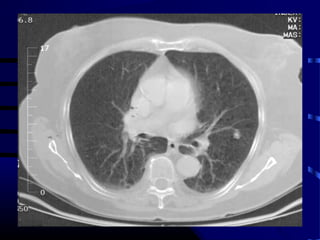

Question

• Patient is a 65 year old smoker with

following CXR and CT scan of chest:

• What test do we order next?